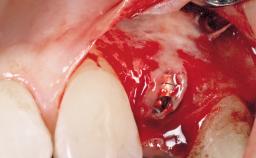

Late Placement of an Implant in a Maxillary Left Central Incisor Site

A 36-year-old female patient was referred for the replacement of the upper left central incisor (tooth 21), which had fractured. Although the tooth had been asymptomatic for many years, the crown began to loosen, at which time she presented to her dentist for an assessment. Teeth 21 and 22 had both been endodontically treated many years previously. She was a healthy individual and a non-smoker.

| Bone Augmentation | Horizontal|Staged |

| Augmentation Materials | Xenogenous|Membrane |

| Soft Tissue Grafting | Simultaneous |